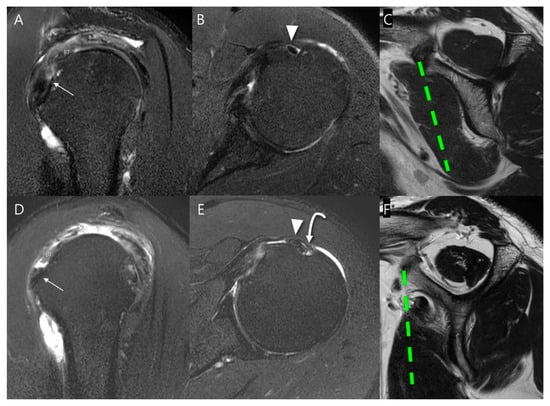

We collected SSC partial thickness tears belonging to Lafosse type 1 on arthroscopy and subclassified them according to the Yoo and Rhee classification (Table 1) using the following parameters (Figure 3) [11]: Yoo type I, leading-edge fraying or longitudinal split; Yoo type IIA, ≤50% detachment of the first facet; Yoo type IIB, >50% detachment of the first facet. It should be noted that, in the Lafosse classification, the surgical indication is defined as a type 2 tear, corresponding to a full thickness tear of the upper one-third. In contrast, the Yoo and Rhee classification defines the surgical indication as Yoo type IIB.

Figure 3.

Subclassification of Lafosse type 1 subscapularis tendon (SSC) partial thickness tears according to the Yoo and Rhee classification. On T2-weighted oblique sagittal images with fat suppression, (A) a normal SSC footprint shows a thin tendinous slip (arrow) in the superior portion, which is closely related to the stability of the biceps tendon (BT). Note that most partial thickness tears (Lafosse type 1) originate from this tendinous slip. (B) Yoo type I tear shows fraying or a longitudinal split at the leading edge (arrow). (C) Yoo type IIA tear is defined as the detachment of less than 50% of the first facet (arrow). (D) Yoo type IIB tear is defined as the detachment of more than 50% of the first facet (arrow).